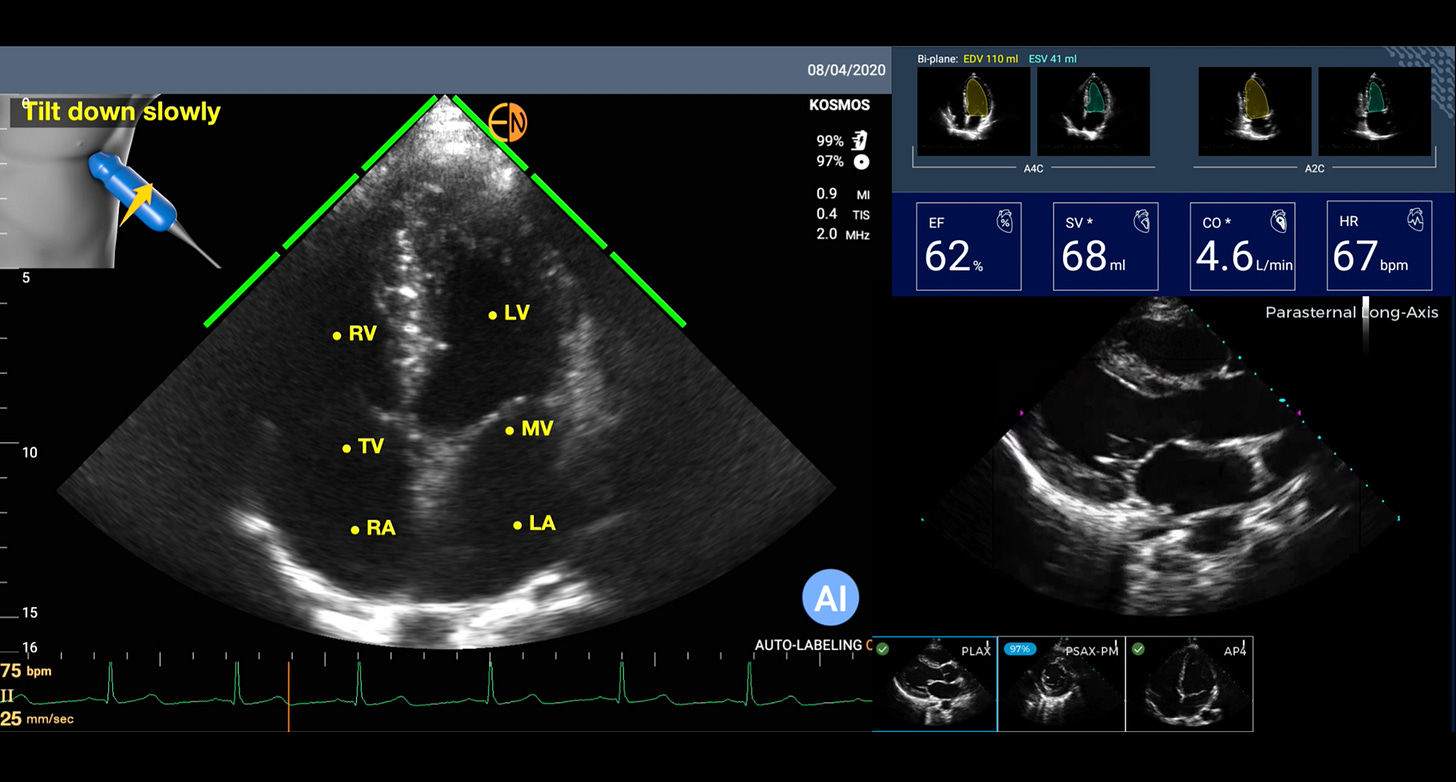

On the clinical side, as a cardiologist, I have used some form of handheld or smartphone ultrasound in place of a stethoscope since 2009. Why? It is obviously far more informative (Figure below) to see the heart, with the dimensions of its cavities, the thickness of the heart muscle, the strength of heart muscle contraction, the structure of the valves, and more, than to listening to heart sounds (something I used to love to do for decades).

But now with A.I. that has changed. For the heart, there are a number of AI tools that will guide a person with no echocardiographic knowledge for acquiring images or interpreting them. All that is needed is for a person to put the smartphone probe on the left side of the chest. Then the AI can tell the person to move it up or down, or clock, or counterclockwise, until it “sees” the heart image and automatically captures it a short video loop. And then automatically labels the structures and provides an interpretation. This sets up the potential for anyone to perform a screening echocardiogram and get an initial reading of it. An example is shown below with automated labeling (LV=left ventricle, LA=left atrium, MV=mitral valve) and providing the ejection fraction (EF%) and other outputs. If this can be done with the heart, the most challenging organ to image because of its motion, you can imagine how much easier it would be for many other organs when just a static shot is needed (like the kidney photo above).